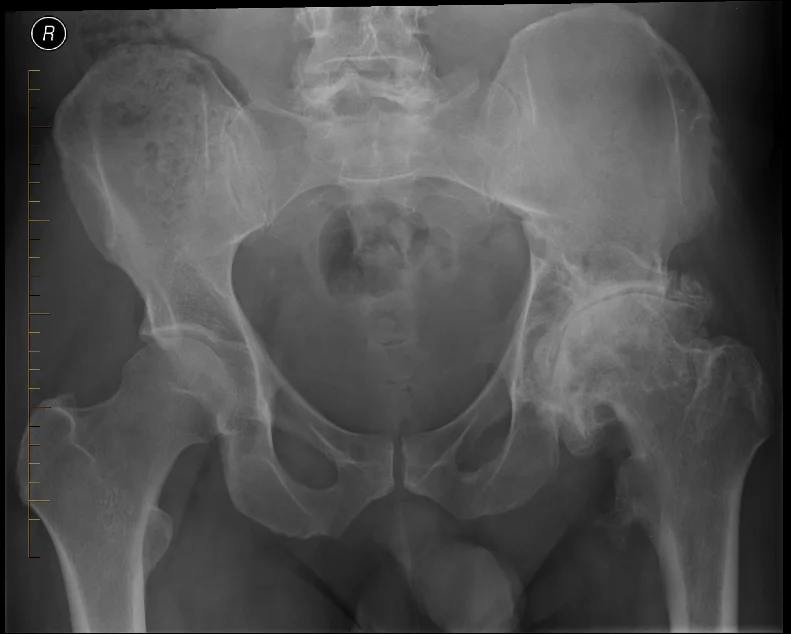

X-ray Imaging

X-rays are the first-line imaging tool for suspected hip arthritis. They help confirm the diagnosis and assess the severity of joint damage. Typical X-ray findings may include:

- Narrowing of the joint space

- Hip bone spurs (osteophytes)

- Changes in bone structure beneath the cartilage

It is important to note that symptoms may exist even when X-ray findings are mild or absent, especially in early disease.